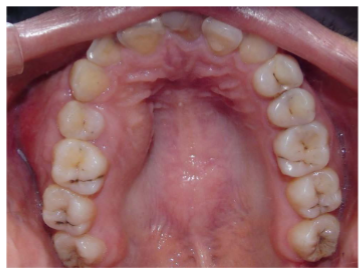

El examen extraoral reveló asimetría facial debida a un abultamiento de consistencia dura y dolorosa que deformaba la fosa canina derecha. El examen intraoral mostraba un tumor de forma redonda que comprometía la zona vestibular y palatina de la pieza 15 y parte de la encía de la pieza 16, había desaparición del fondo del surco vestibular, a la palpación el tumor tenía consistencia dura y la paciente manifestaba dolor de intensidad leve, el tamaño aproximado era de 3 x 2,5 x 2 cm, la mucosa que recubría la lesión lucia normal (figura 1). Se notó la ausencia de la pieza 14, las pruebas de vitalidad pulpar de las piezas 13, 15 y 16 resultaron normales. Las coronas de los dientes adyacentes estaban conservadas en forma y tamaño y no existía movilidad dental, la pieza 15 estaba ligeramente sumergida, pero la oclusión estaba conservada.